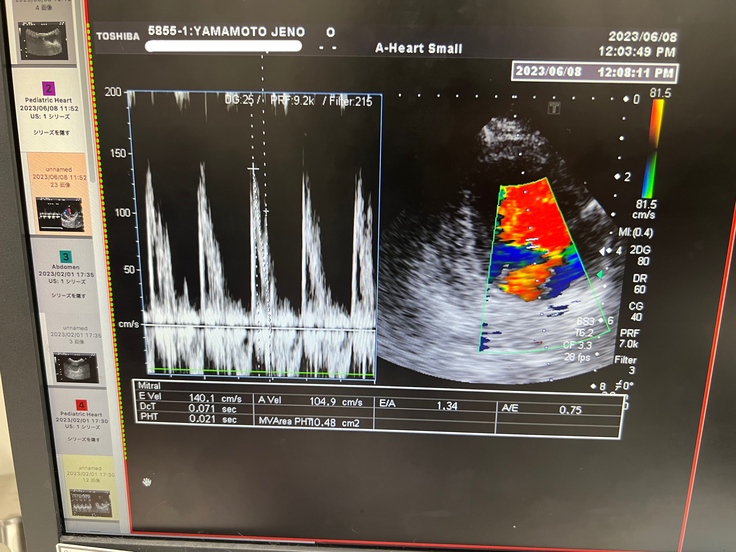

※心臓のエコー写真